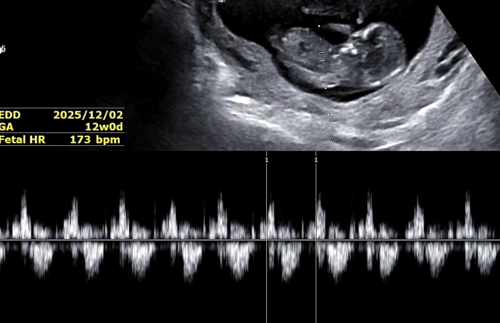

1차 기형아 검사, 목투명대 확인 12주

9주 때 추추의 심박수가 빠른 편이라 심박수가 정상대로 내려왔기를 바라며 병원을 방문했습니다.

저번에는 젤리곰의 형태를 하고 있었는데, 이제 얼추 사람의 형태를 보이고 있어요.

입체 초음파도 보고 심박수도 173 bpm으로 확인!

다행히 심박수가 떨어졌어요. 정상 범위로 돌아왔답니다.

목투명대도 1.14센티로 정상이었어요.